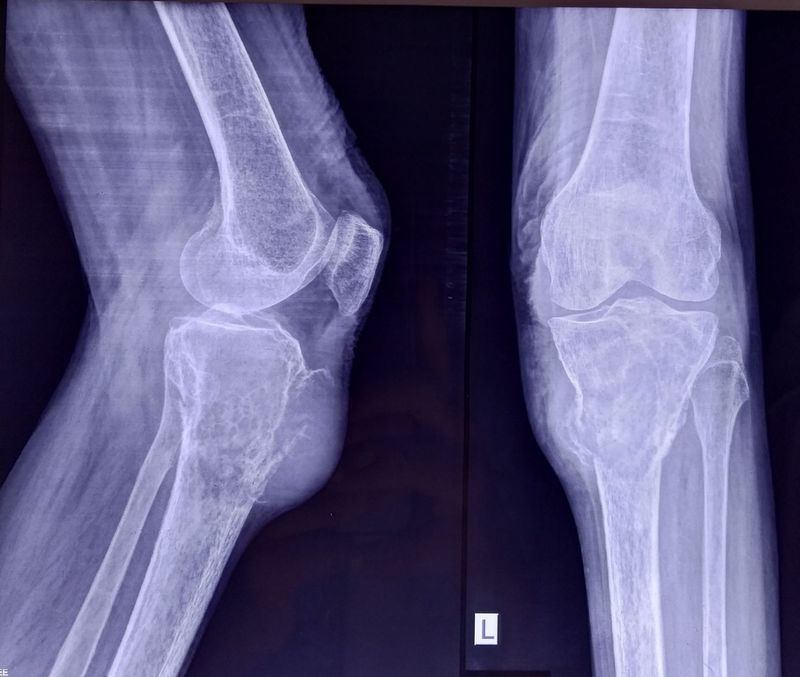

What's your diagnosis?